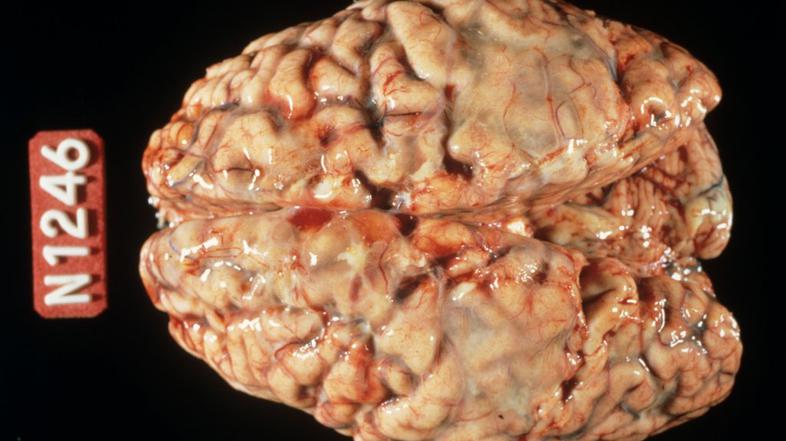

Meningitis možgani Profimedias

KME je resna bolezen osrednjega živčevja. Najučinkovitejša zaščita pred njim je cepljenje, jesenski čas pa najprimernejši za prvi odmerek cepiva.